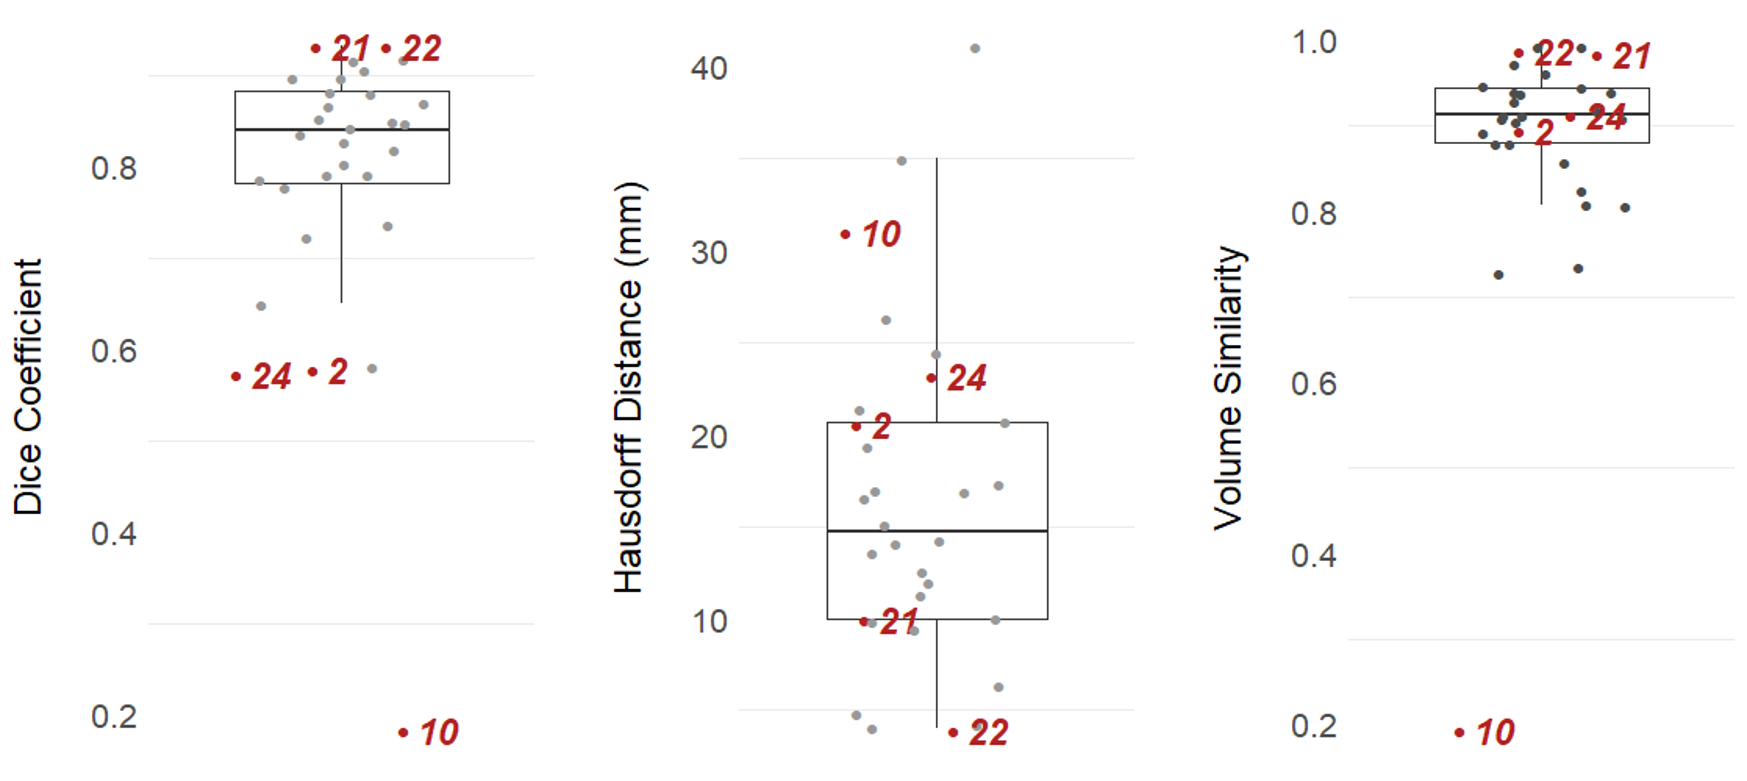

Figure 2 illustrates the quantitative results of the segmentation performance on the 30 cases of the dataset. Every dot corresponds to a sample. The ones marked with numbers are selected according to their achieved Dice score. The selection contains the two best (samples 21 and 22) and the three worst performing cases (samples 10, 24, 2). Table 2 shows a statistical summary of the results. The proposed method achieved a median Dice of . This is close to the variability in the manual expert delineations, which has a median Dice coefficient of .

Figure 3 visualizes the segmentation results for the selected samples. The first and second row correspond to the best-performing cases. Their segmentation is close to ground truth and the uncertainty is mainly present at the boundary between foreground (i.e., cavity) and background. In contrast, samples 2, 24, and 10 show the worst performances. The network is struggling with the inhomogeneous cavity of sample 2. There is no clear delineation in the input sequences, which makes the task difficult. Sample 24 is most probably flawed because of the erroneous registration (compare T1 and T2 in Figure 3). Sample 10 is failing although the cavity is clearly visible in the T1 and T2 sequence. Further analysis of this case pointed to a particular hypointense cavity in the FLAIR sequence which appears isointense to cerebrospinal fluid and might confuse the network. Additionally, all three cases yielded increased uncertainties.